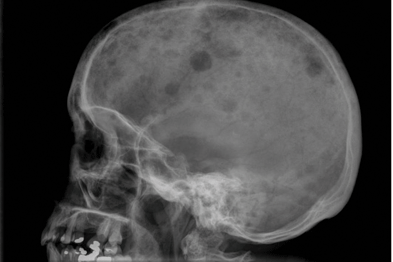

Multiple Myeloma and Dentistry Lateral Skull view showing multiple punched out radiolucent lesion residual multiple myeloma or another malignancy; hypoproteinemia; renal impairment from disease or drugs; and/or chemotherapy. ... Access This Document